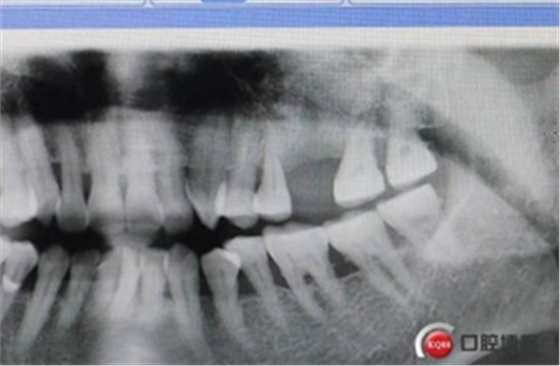

大家好,我是梁老師的助理小依。由于梁老師每天手術(shù)檔期安排較滿,加上經(jīng)常出差講課,沒有時間整理病例 。為了方便大家更及時的了解梁老師最新手術(shù)動態(tài),以后將由我為大家整理并推送梁老師最新經(jīng)典案例。案例文字旁白少,但圖片會盡量完整展示手術(shù)全過程,供大家學(xué)習(xí)參考。有任何問題,可以留言,梁老師會親自為大家解答。感謝大家對梁老師的支持和關(guān)注!